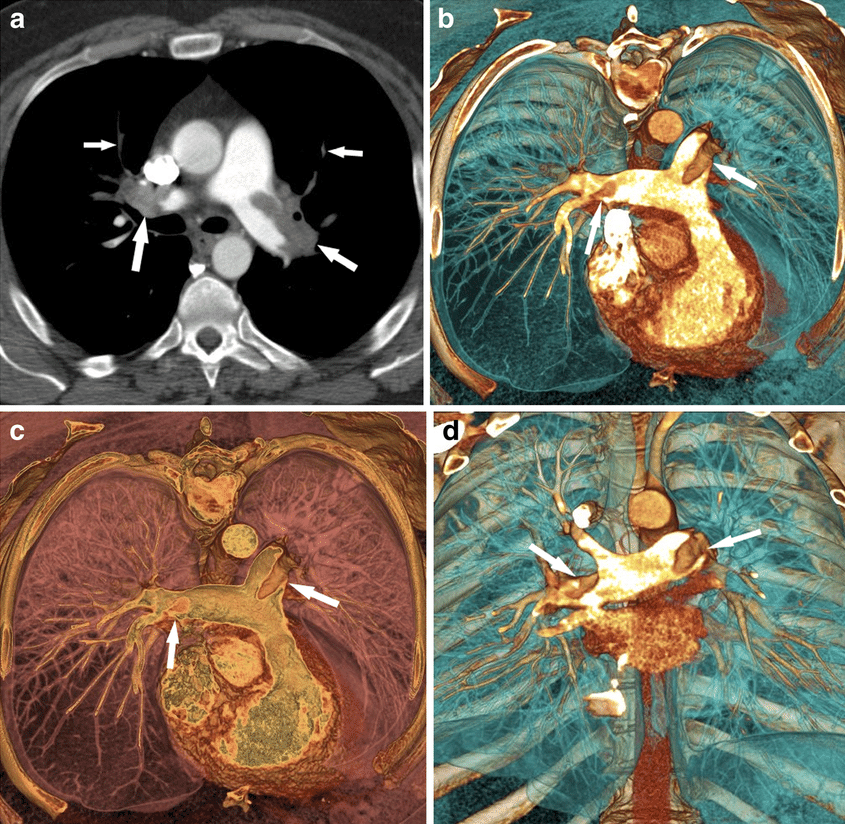

肺栓塞的ct诊断

图片尺寸1080x810